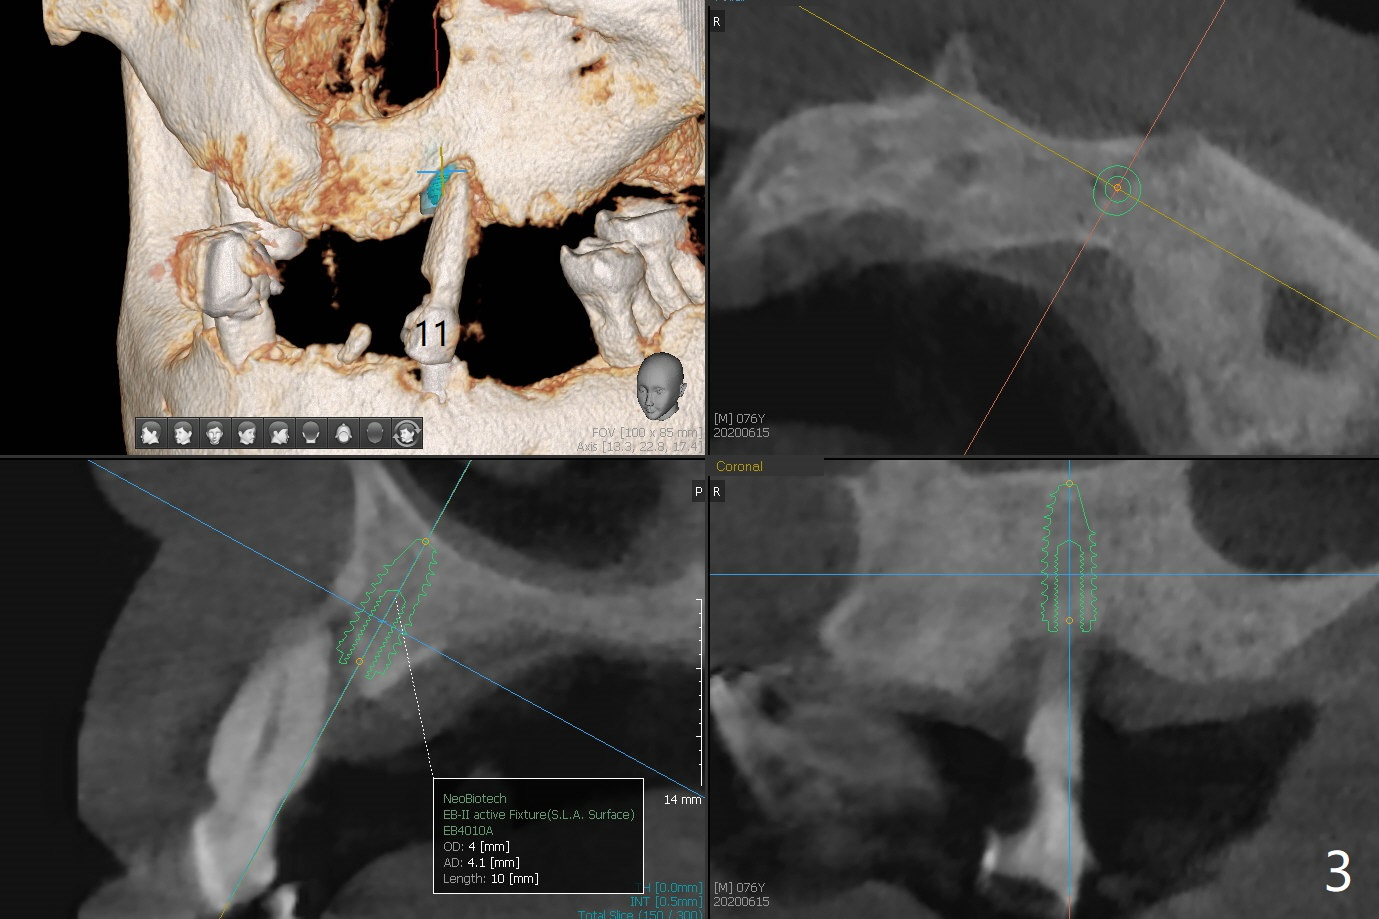

A 76-year-old man returns to clinic with chief complaint of loose top partial 2 years 3 months post #21 implant placement (Fig.1,2). The tooth #11 has mobility, while the socket of #13 heals and the tooth #1 is stable and functional (Fig.1). Two implants will be placed at #11 and 13 (Fig.3,4) with ball abutments (4 and 2 mm cuffs, respectively). Since the bone density is low at #13, bone expanders will be used as well as for sinus lift (implant 4x10 mm instead, PRF). Keep the tooth #11 as a denture one. Soft reline will be used to hold the abutments.